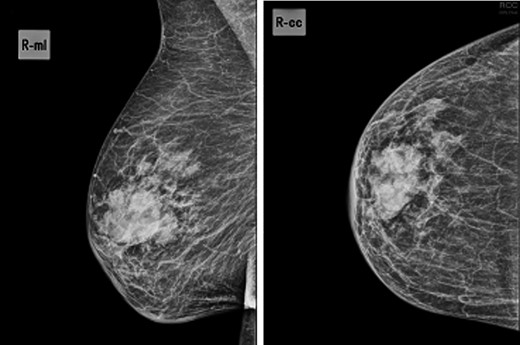

Mammogram—44.5 × 24.5-mm nodular lesion in the transition of the external quadrants of the right breast with lobulated contours and associated skin thickening.

We present an 88-year-old female patient with past medical history of pulmonary tuberculosis, peripheral venous insufficiency and asthma. There was no personal or family history of cancer, namely breast cancer. The patient was referred due to a lump detected in the right breast. On observation, the patient presented with a palpable mass in the transition of the external quadrants of the right breast with 50 mm in diameter, hard, mobile, non-adherent to the skin or the underlying tissue, as well as a suspicious axillary adenopathy. A mammogram was performed and the lesion was described as a nodular lesion with lobulated contours, with 44.5 × 24.5 mm and associated skin thickening (Fig. 1). On ultrasound, the lesion corresponded to a hypoechoic nodule with lobulated and poorly defined contours as well as with multiple ipsilateral axillary adenopathies, the largest with 20 mm—breast imaging-reporting and data system (BI-RADS 5). A core biopsy of the breast lesion and suspected axillary adenopathy were performed, both consistence with diffuse large B-cell lymphoma, positive for CD20, BCL2, BCL6 and MUM1 (Fig. 2). Nuclear immunostaining was observed in about 90% of neoplastic cells. On staging CT scan, no lesions were found than those already described (Fig. 3). The patient was submitted to R-mini-CHOP (CHOP and Rituximab), completing three cycles, with clinical and radiological response.